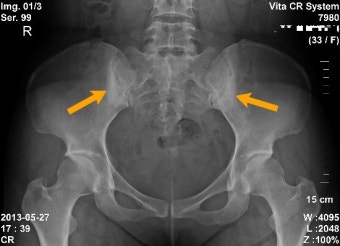

| 엉덩이·골반 통증 | 천장관절염 증상, 한쪽 또는 양쪽 반복 |

- X-ray: 천장관절 이상 확인